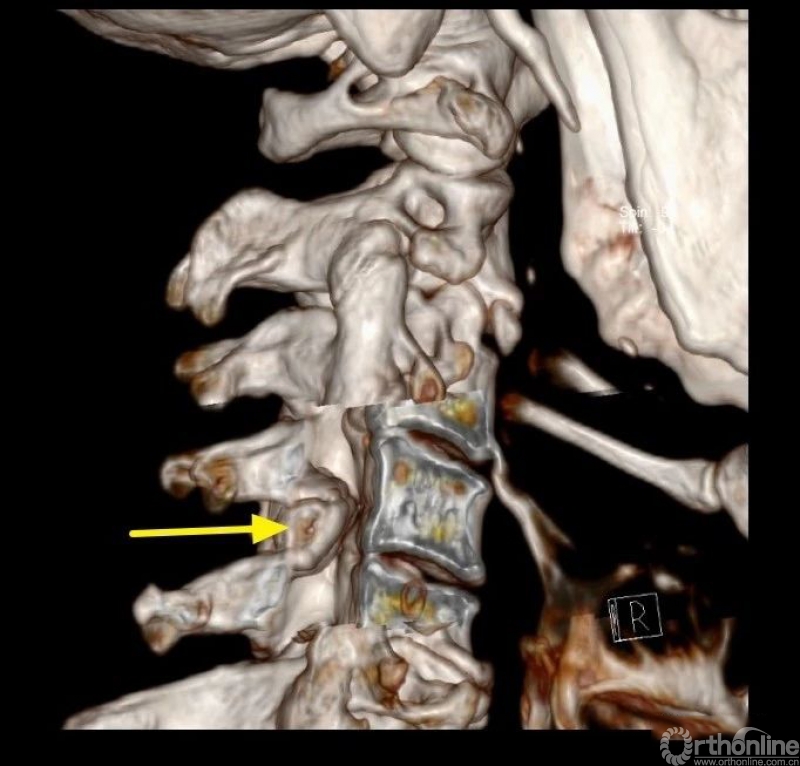

入院查体患者四肢肌张力高,双侧hoffman阳性。CT及MRI检查提示C4/5左侧关节突内缘有一巨大骨块(15mm*16mm),相应节段椎管严重狭窄。椎管内骨块的前端还有一游离骨块。

影像学资料

因患者骨块位于左侧,故而本病例选择右侧入路(即对侧颈椎ULBD)。

选择对侧入路的原因:

1.术前评估骨赘侧的椎板间隙几乎完全消失,镜下识别解剖标志困难;

2.在完全看不到骨赘底面的神经结构的情况下磨除骨块风险较大,且神经结构无退路;

3.对侧先椎板切除减压给神经结构一缓冲空间更加安全,并且整个骨块的内侧及上缘、下缘清晰可见。